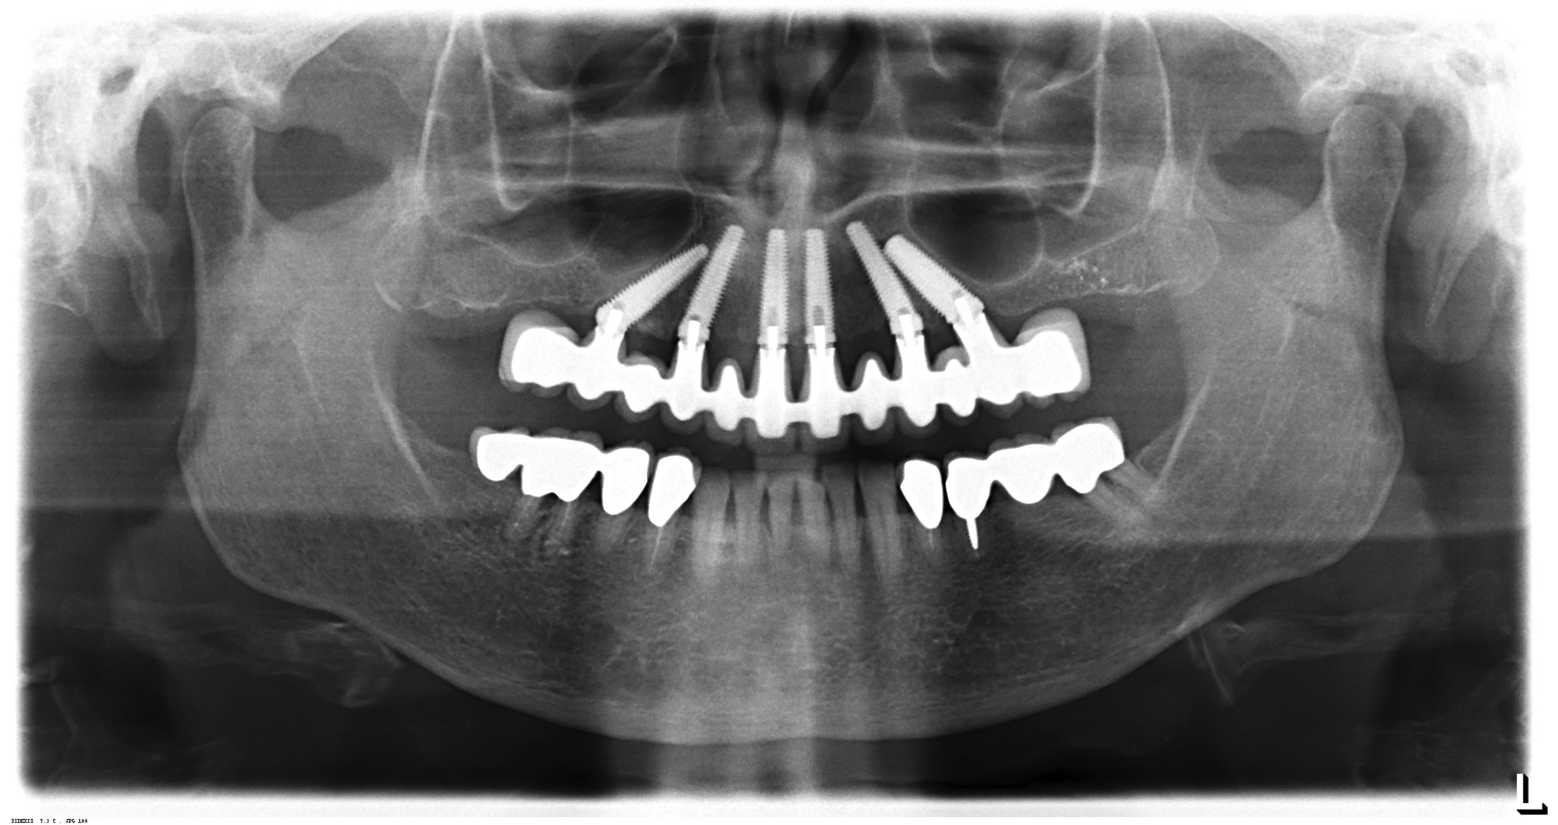

Fig 11. Panorex of clinical application of dual-axis principles. From left to right: 36-degree tooth No. 4; 24-degree tooth No. 6; 12-degree tooth No. 8; 12-degree tooth No. 9; 24-degree tooth No. 11; and 36-degree tooth No. 13. Angulation is designed to avoid maxillary sinus and buccal constraints of the anterior maxilla. (Image courtesy of Costa Nicolopoulos, BDS, Dubai, United Arab Emirates)

Figure 11

The author has used the dual-axial implant fixture unconventionally in the anterior mandible in an orientation that avoids perforation into the floor of the mouth (Figure 8).5 Dual-axial implants have also been used to avoid critical anatomic structures, such as the maxillary sinuses (Figure 9) and inferior alveolar nerves (Figure 10),47 thereby reducing the need for grafting procedures. Because these implants have subcrestal angular correction, they can be used with standard uniaxial abutments in a common path of insertion, thus enabling screw retention.

With the increased application of this concept, more options have been introduced, including 24-degree and 36-degree correction (Figure 11 through Figure 13). At present, larger angular corrections are available with external hexagon connection systems, while the 12-degree connection is also available in most internal connection configurations.